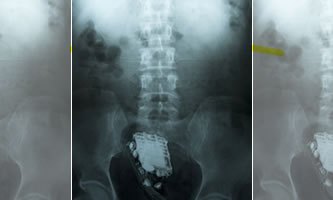

Estudante é flagrada no Urso Branco com “Kit love” escondido na vagina